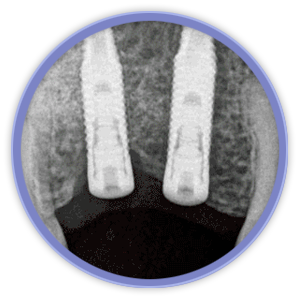

El aspecto más revolucionario en este ámbito fue la aparición de los implantes dentales que son unos pequeños bloques de titanio, con forma de raíz dental, que se insertan dentro del hueso mandibular o maxilar del paciente y sirven de sujeción para dentaduras, puentes o coronas, mejorando así la calidad de vida y aumentando las posibilidades de tratamiento de los pacientes.

La magnificación de la imagen mediante lupas o microscopio dental nos permiten niveles de acabado y de precisión mucho más exigentes. Actualmente la importancia de la estética gingival (encías), ha obligado a desarrollar técnicas de regeneración de hueso y tejidos blandos, que complementan a las cirugías de implantes entre otras.